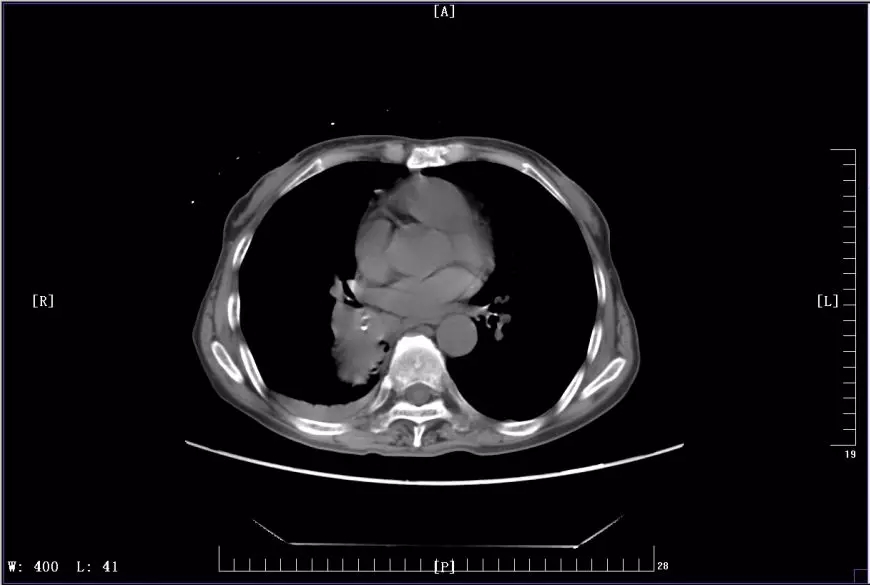

下圖是徐麗參加KEYNOTE-407臨床試驗(yàn)前后CT影像對(duì)比圖:

2017年11月治療前CT影像